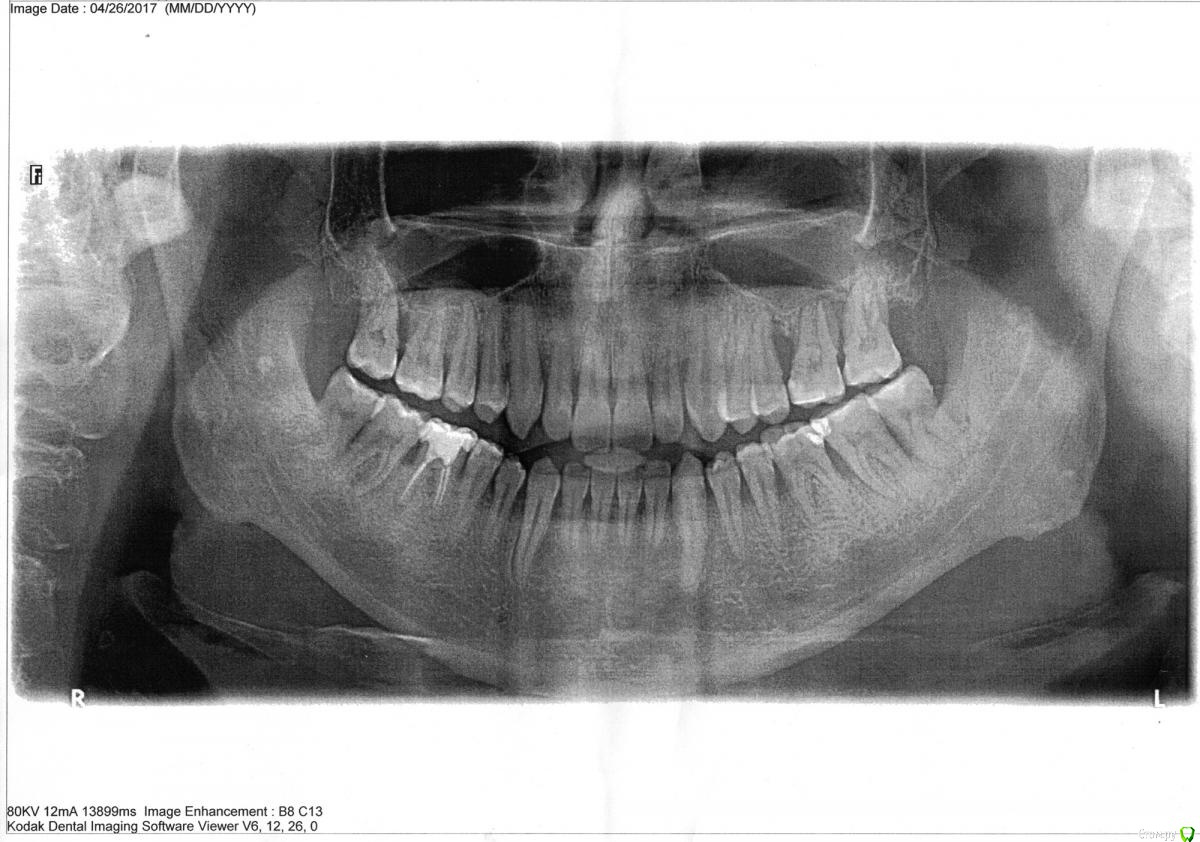

нескучный пациент Опубликовано 2 мая, 2017 Поделиться Опубликовано 2 мая, 2017 Здравствуйте, периодически мучают флюсы на деснах, недавно обстоятельства усугубились - обратился к стоматологу в поликлинику она рекомендовала найти хорошего пародонтолога.Что сейчас происходит: подвижность нескольких зубов (на панорамном снимке с правой стороны три верхних зуба), кровотечения. Опухлость между 33 и 34 зубом, есть язвочка и постоянно выделяется гной между этими зубами, также на десне (под десной) внизу 33 зуба есть белая твердая выпуклость.Пока ищу пародонтолога, делаю аппликации метрогил-дента и полоскаю рот раствором соды и соли, процедуры делаю четвертый день.Может быть сходить к стоматологу терапевту? Как найти хорошего пародонтолога? Можно ли восстановить костную ткань между зубами? Какие процедуры могут помочь? Плазмолифтинг для десен это плацебо? Ссылка на комментарий